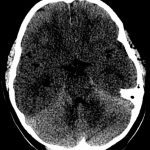

Indication: Seizure

Findings

- Diffusely hypodense appearance of the supratentorial gray matter relative to the cerebellar gray matter with few, if any, visible cerebral sulci

- Partially imaged occipitocervical fusion hardware

Diagnosis

- Diffuse cerebral edema

Diffusely hypodense appearance of the supratentorial gray matter relative to the cerebellar gray matter with few, if any, visible cerebral sulci, which raises concern for diffuse cerebral edema. Gray-white differentiation is largely preserved. Recommend brain MRI for further evaluation.

No acute hemorrhage, midline shift/herniation, or hydrocephalus.